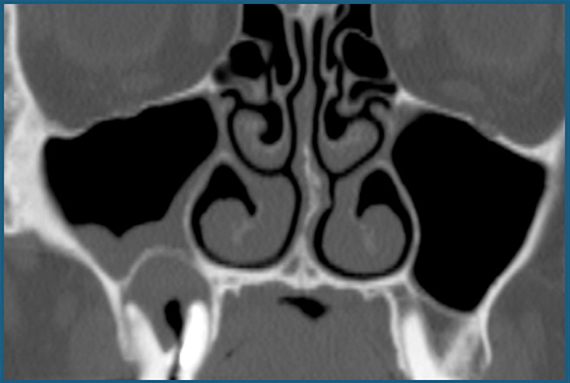

Dans le détail, Jean-François Papon, médecin chef du service ORL au centre hospitalier universitaire du Kremlin-Bicêtre, ouvrira cette journée avec la présentation des fondamentaux. Il rappellera les subtilités anatomiques du sinus et nous apprendra à repérer, grâce au bon examen radiographique, les images types à ne pas manquer.

- Lecture de l’imagerie sinusienne : repérer les structures et anomalies anatomiques

- Prescription radiographique et médicamenteuse

- Analyse radiographique préopératoire en implantologie

- Savoir analyser les radiographies sinusiennes